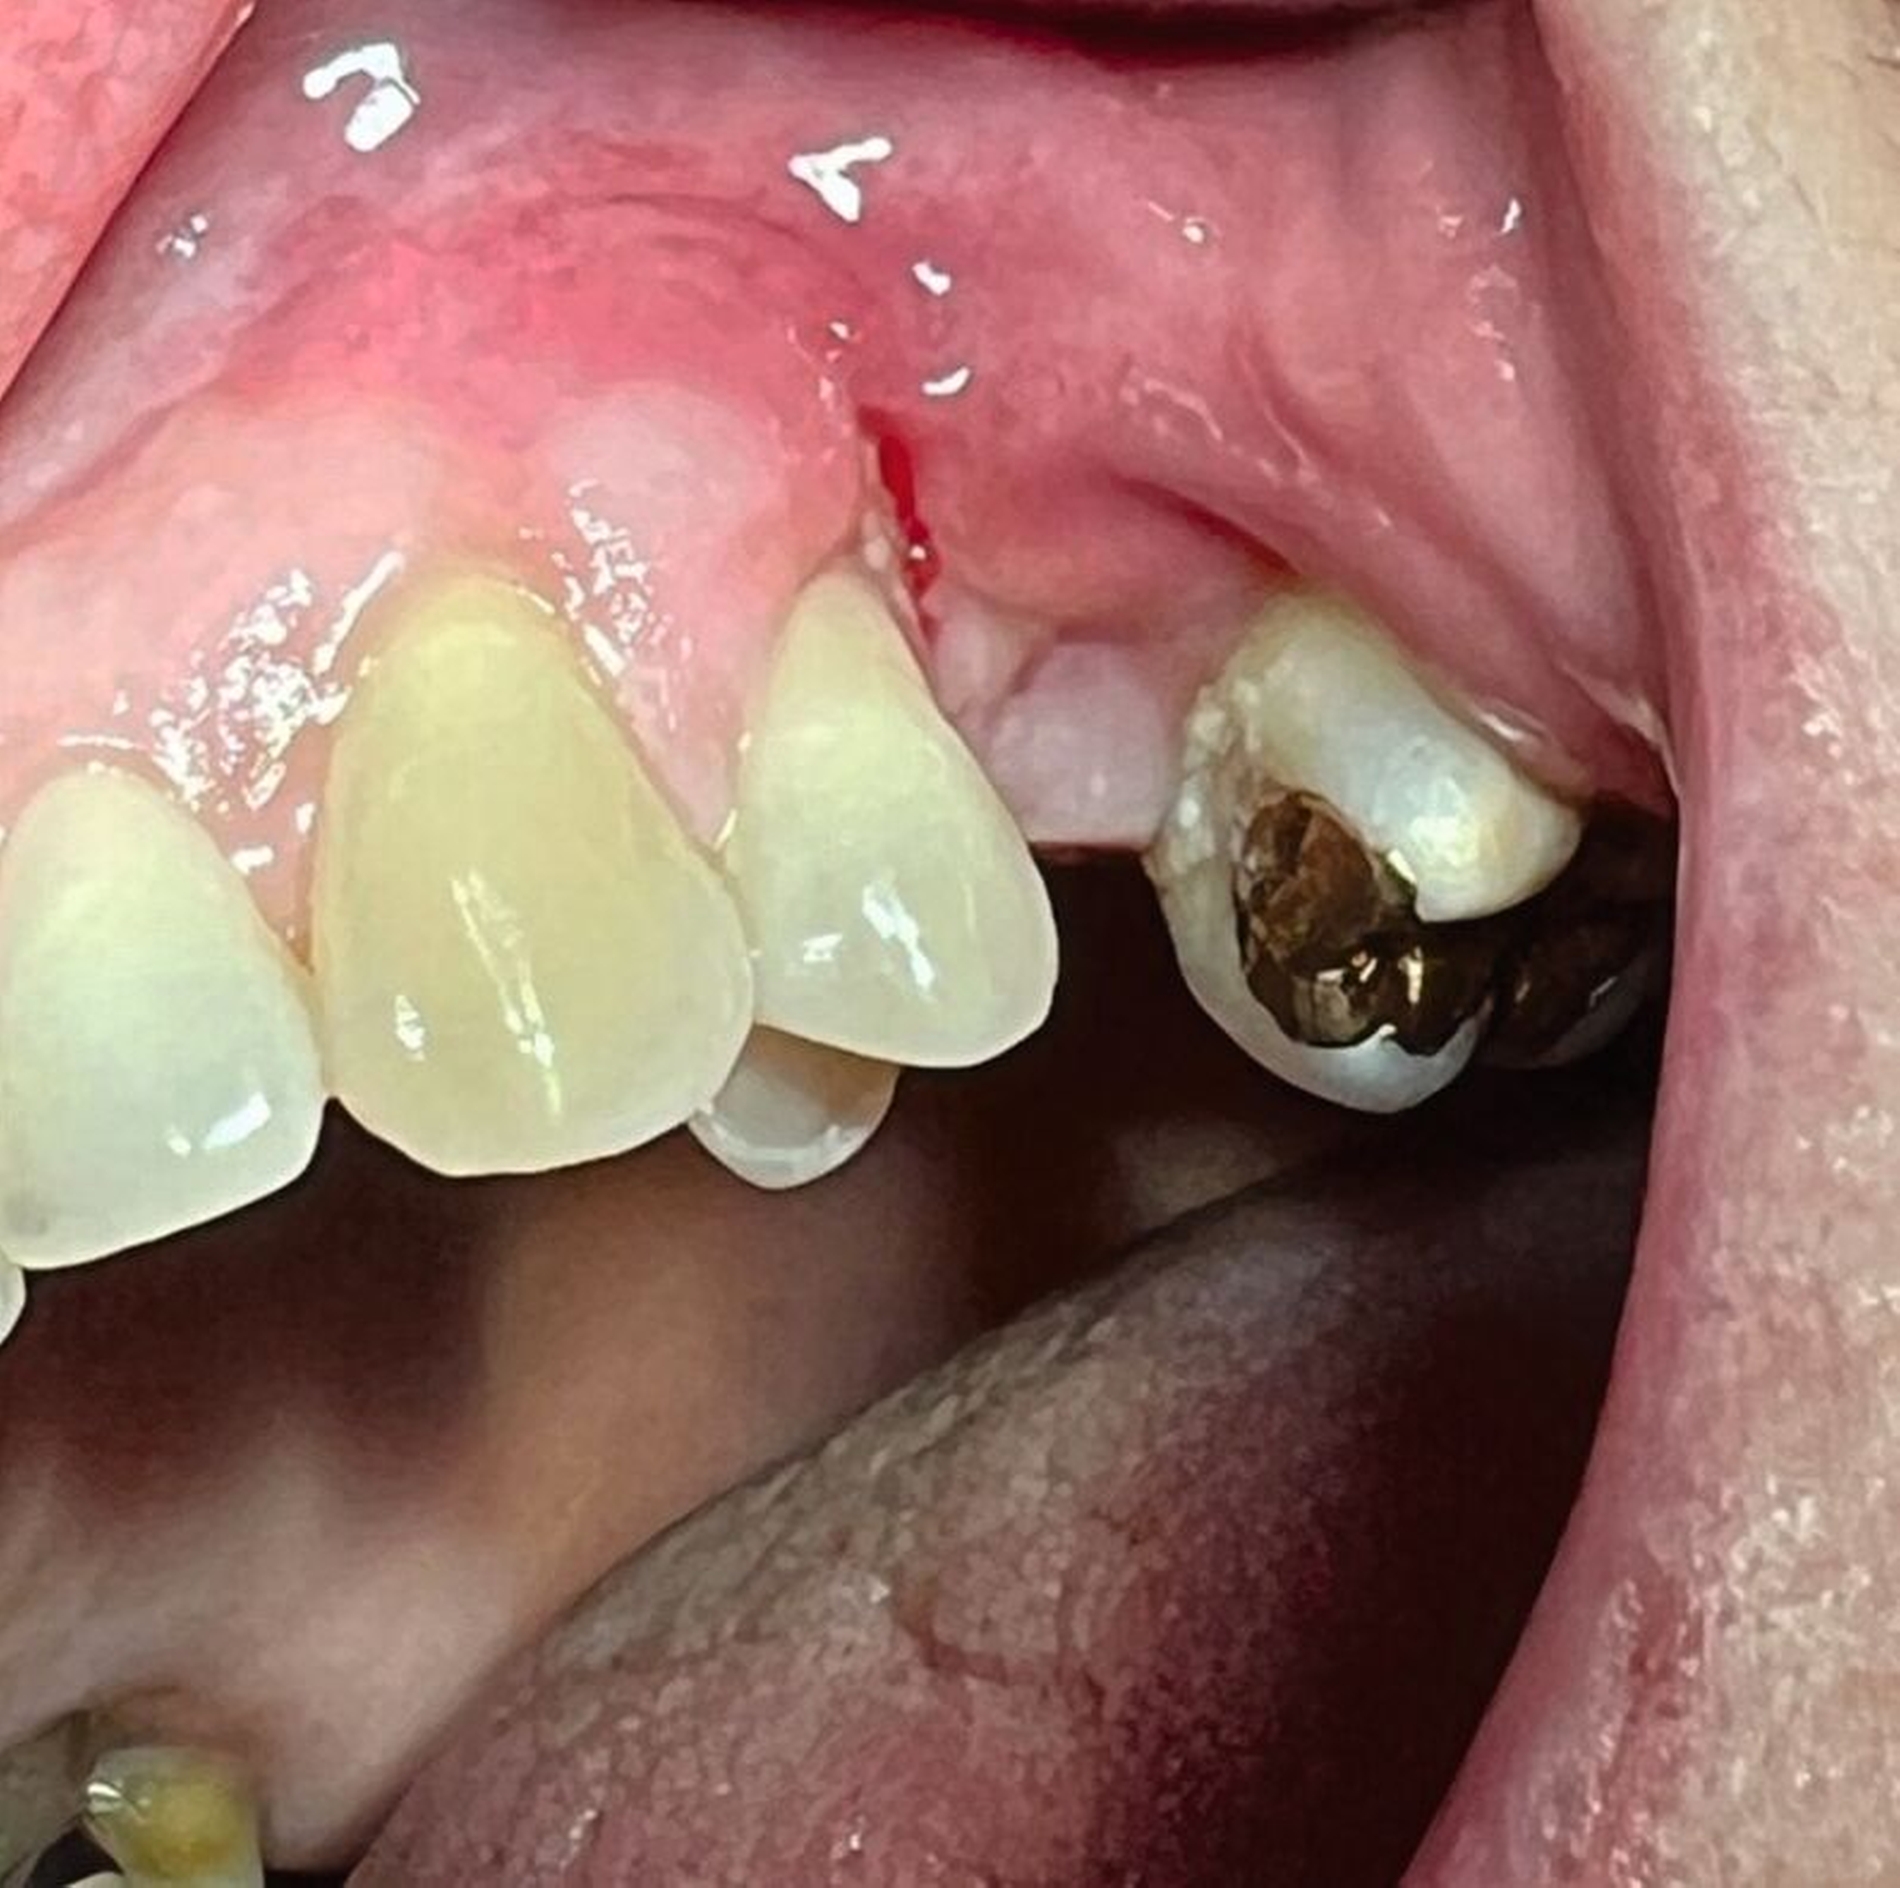

Klinisch zeigte sich derZahn 25 perkussionsempfindlich mit Lockerungsgrad II (der ja bereits vor der Wurzelbehandlung vorhanden war). Der umgebende Knochen war exponiert und nekrotisch, jedoch schmerzfrei (Abbildung 1). Der Vitalitätstest mit Kältespray ergab keine Reaktion an Zahn 24, während die Zähne 26 und 23 vital reagierten. Aufgrund der ausgedehnten Nekrose und der vorhandenen Zahnlockerung entschieden wir uns im Einvernehmen mit der Patientin für die chirurgische Entfernung des Zahnes sowie des nekrotischen Hart- und Weichgewebes. Die Patientin wurde ausführlich über die Risiken des Eingriffs (Schmerzen, Schwellung, Nachblutung, Nervverletzung, mögliche Eröffnung der Kieferhöhle, Schädigung benachbarter Strukturen) aufgeklärt und erhielt einen entsprechenden Aufklärungsbogen.

Das präoperative OPG zeigte einen generalisierten horizontalen und an den Zähnen 16 und 26 auch einen vertikalen Knochenabbau, Konkremente insbesondere im zweiten und im dritten Quadranten und in der Unterkieferfront, einen Füllungsverlust an 22, eine regelrechte Wurzelkanalbehandlung an Zahn 25, aber keine weiteren Auffälligkeiten in den umgebenden radiologischen Strukturen (Abbildung 2). Unter antibiotischer Abschirmung wurde der nekrotische Knochen einschließlich des Zahnes 25 bis zum vitalen, durchbluteten Gewebe in Lokalanästhesie abgetragen (Abbildung 3). Der Wundverschluss erfolgte mittels eines Dehnungslappens durch Periostschlitzung (Abbildung 4). Es folgte eine detaillierte Instruktion zur postoperativen Wundschonung. Eine Röntgenkontrolle wurde postoperativ durchgeführt (Abbildung 5).